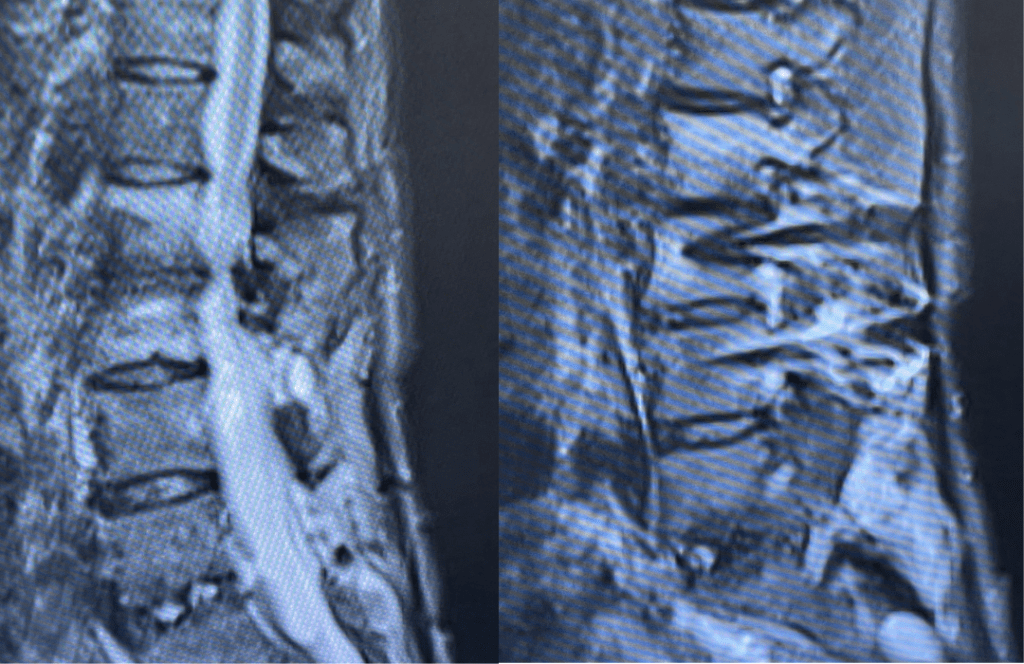

This 62-year-old female presents with chronic intractable low back pain with radiation down the front of her thighs. The patient had had two prior fusion surgeries: She initially had an L4-S1 fusion twelve years prior and a subsequent revision extension of her fusion at L3-4 that she had three years prior. She had a long-term history of smoking. She had mild hip flexor weakness, right greater than left. Imaging studies revealed next segment degeneration and stenosis at L2-3 (Figs. 1a and 1b and 2).

Figure 2. Axial T2 MRI of the lumbar spine demonstrating L2-3 stenosis due to significant facet arthropathy.